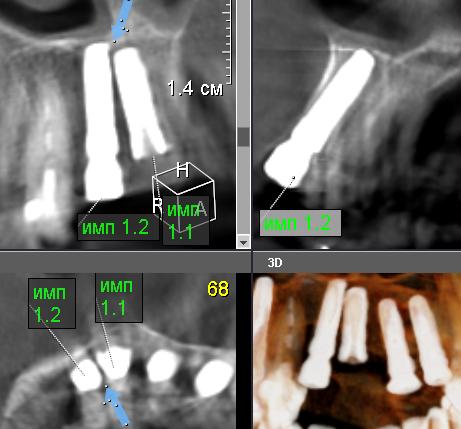

Судебная комплексная медико-оценочная экспертиза, направленная на всесторонний анализ качества и соответствия нормативным требованиям оказанных стоматологических услуг, включая дентальную имплантацию зубов № 46, 36, 22, 21, 15, 12, 11. В рамках исследования проводился детальный анализ представленной медицинской документации, рентгенологических данных (включая КЛКТ), а также сопоставление их с действующими клиническими рекомендациями и стандартами медицинской помощи. Целью являлось определение правильности и своевременности медицинских манипуляций, выявление потенциальных нарушений и недостатков в процессе лечения, а также оценка потребностей в дальнейшем терапевтическом вмешательстве и его приблизительной стоимости для устранения выявленных недочетов.